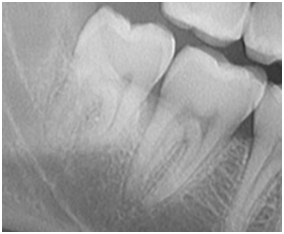

それでは早速ですが、レントゲン画像を用いて説明していこうと思います!

それぞれの画像の左側の歯が、親知らずになります。1枚目の親知らずは、隣の歯(第二大臼歯)と同じレベルの高さまで萌出しています。2枚目の親知らずは、2枚目と同様に横向きで隣の歯に衝突していますが、やや浅い位置で埋まっている状態です。1枚目の親知らずのように、正常に萌出できれば特に問題はないのですが、現代人は顎が小さくなり、奥のスペースが不足しているため、最後に生える親知らずが、2枚目の画像のように隣の歯に衝突し、斜めや横向きに埋まったままになるケースも少なくありません。先天的に親知らずが存在しないケースも含めると、おおよそ4人に1人は、親知らずが生えてこないというふうにも言われています。